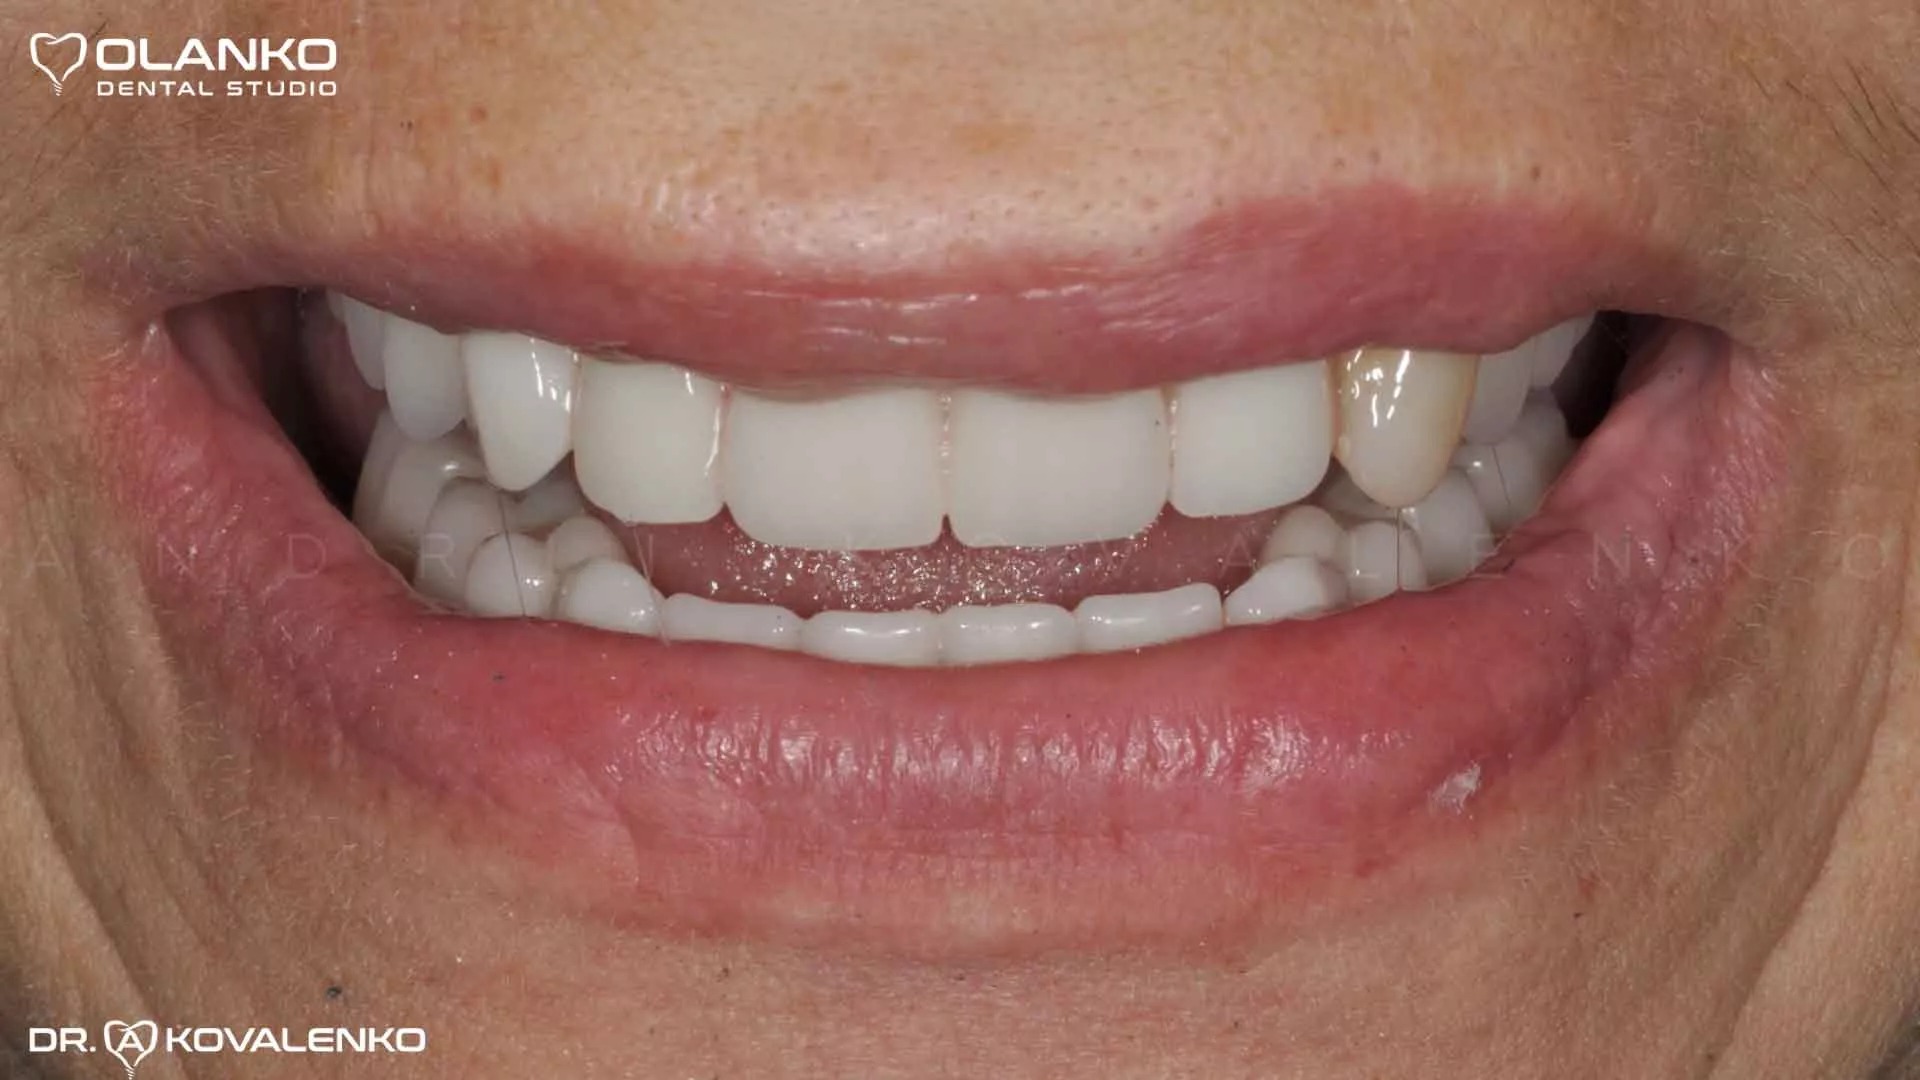

Фото протез установлен прикручен к имплантатам

Клинический случай 9 имплантация зубов